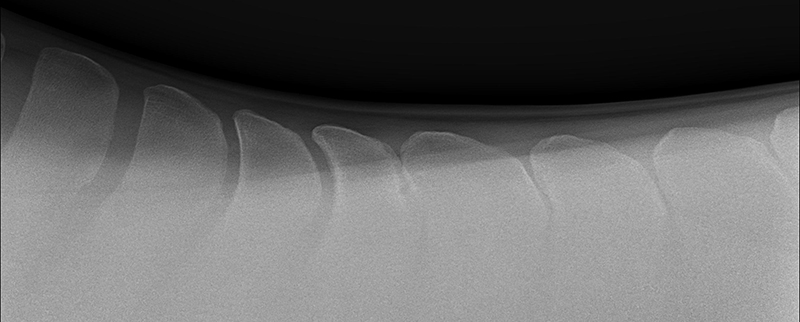

HORSE “A” PRE-OP X-RAY

Shows Impingement of the Dorsal Spinous Processes

HORSE “A” IMMEDIATELY POST-OP X-RAY

Shows Corrected Dorsal Spinous Processes After Bone Reduction Procedure Performed by Dr. Cliff Honnas

HORSE “A” 3-YEAR POST-OP X-RAY

Shows Lasting Results from Bone Reduction Procedure Performed by Dr. Cliff Honnas

The second surgical option considered for Kissing Spines patients is a bone reduction procedure. Dr. Honnas is recognized as one of the foremost experts in the country at performing this procedure and garnering impressive long-term results for Kissing Spines patients.

“The bone reduction surgery that I do removes bone at each impinging space, then recreates a space between those adjacent bones,” says Dr. Honnas of the surgical method. While some practitioners prefer to perform this procedure on the standing horse, Dr. Honnas’ preference is to operate on these cases under general anesthesia laying left-side down. A primary reason for this preference is that the position of the horse alleviates the weight of the gut, so it no longer pulls the dorsal spinous processes closer together. “I pull them to the edge of the table, make an incision right on the midline and cut through the skin. I then cut through the dorsal spinous ligament (the ligament over the top of the backbone) and cut away the muscles on either side of the dorsal spinous processes,” he explains of his technique technique. “There’s no way to take away that bone without removing the ligament. Next, I cut the interspinous ligament that's between each dorsal spinous process, then using my right hand with a pair of bone-cutting forceps, I cut away on the bone that's behind each impinging space. I cut a piece, and I feel with my left index finger. I’m removing the interspinous ligament and the front edge of the backbone at each impending space.” It’s a gradual process where Dr. Honnas cuts, feels, cuts, feels and so on, being sure to trim up any rough edges on the bone as he goes. “When finished, I can get my index finger between the bones all the way down to where the space opens up again. Usually, they’re going to be pretty tight for about 1.5 to 2 inches, then open up naturally below that,” he says of the anatomy of the back following surgery.

The number of bone reduction procedures that Dr. Honnas performs has risen dramatically in conjunction with improved diagnostics and veterinary familiarity of Kissing Spines. Performing roughly 145 of these procedures in the last year on horses from every corner of the country, Dr. Honnas and his team are known for their exceptional track record. “I tell my clients, if this is a confirmed case of Kissing Spines, then this surgery will fix your horse,” he says with confidence. He and his team have achieved a 90 percent success rate, allowing patients to go on to live and compete free of the pain they once endured as a result of Kissing Spines.